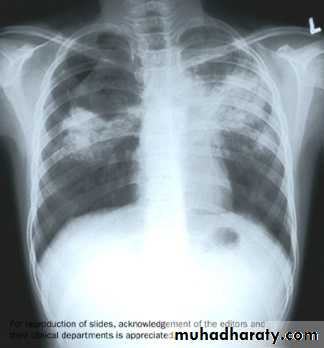

Diagnosis and Treatment for Latent & Active TBTools for Diagnosing TB InfectionChest X-Ray

A chest x-ray is ordered when a person presents a recent skin test conversion and is suspected of having TB.

If a chest x-ray is normal, further diagnostic testing may not be necessary.

If the chest x-ray shows signs of disease, further diagnostic testing will be needed to confirm TB disease.